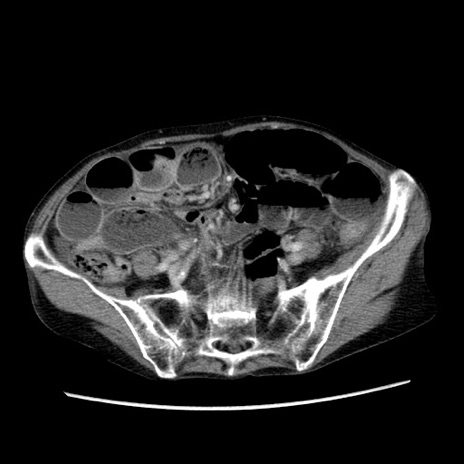

症例25(横断像)

【症例】80歳代女性

【主訴】胸のつかえ感

【現病歴】約9時間前に食後から胸のつかえた感じあり、嘔吐あり、来院。

【既往歴】胃癌(全摘)、胆摘、虫垂炎

【身体所見】心窩部に圧痛あり、反跳痛なし。

【データ】WBC 5700、CRP 0.05